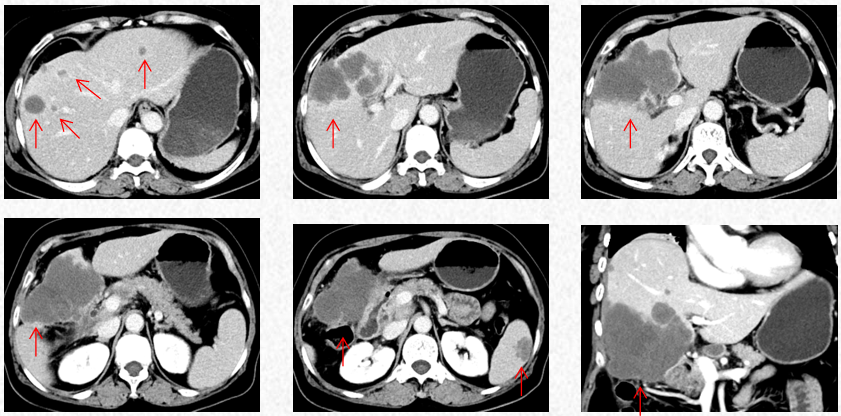

2022-10-9中南大学湘雅二院行PET/CT:肝左内叶和右前叶糖代谢增高肿块(最大横截面积10*8cm,SUVmax17.9),考虑恶性肿瘤(肝癌?胆囊癌累及肝脏?),累及胆囊及结肠肝曲及周围腹膜腔。肝门、门腔静脉间、右中腹(大网膜走行区)多发糖代谢增高的肿大淋巴结(大者约13*20mm,SUVmax 8.6),考虑淋巴结转移。盆腔子宫左后方糖代谢增高结节灶(最大横截面积15*14mm,SUVmax11.3),考虑转移所致(卵巢转移?腹膜转移)。

2022-10-9中南大学湘雅二院PET/CT

2022-11-30复查胸腹CT提示进展(PD)。

2022-11-30胸腹CT:肝肿物最大横截面积107*80mm(原病灶10*8cm),腹腔淋巴结最大10mm。新发脾脏转移瘤大小27*15mm。